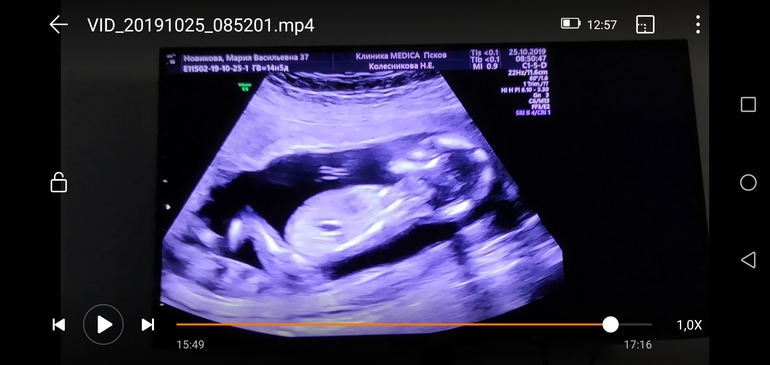

Да, всё верно. Врач долго меня мурыжила и на бок и на спину, хотела пол показать, я же платно скрининг повторно делала и вот предположила нам мальчика. Только снизу, якобы, рассмотрела.

А выше фото, это с видео этого же скрининга.

Снизу прям мальчик, а сверху девочка... Желаю вам чтобы это оказалась дочечка)